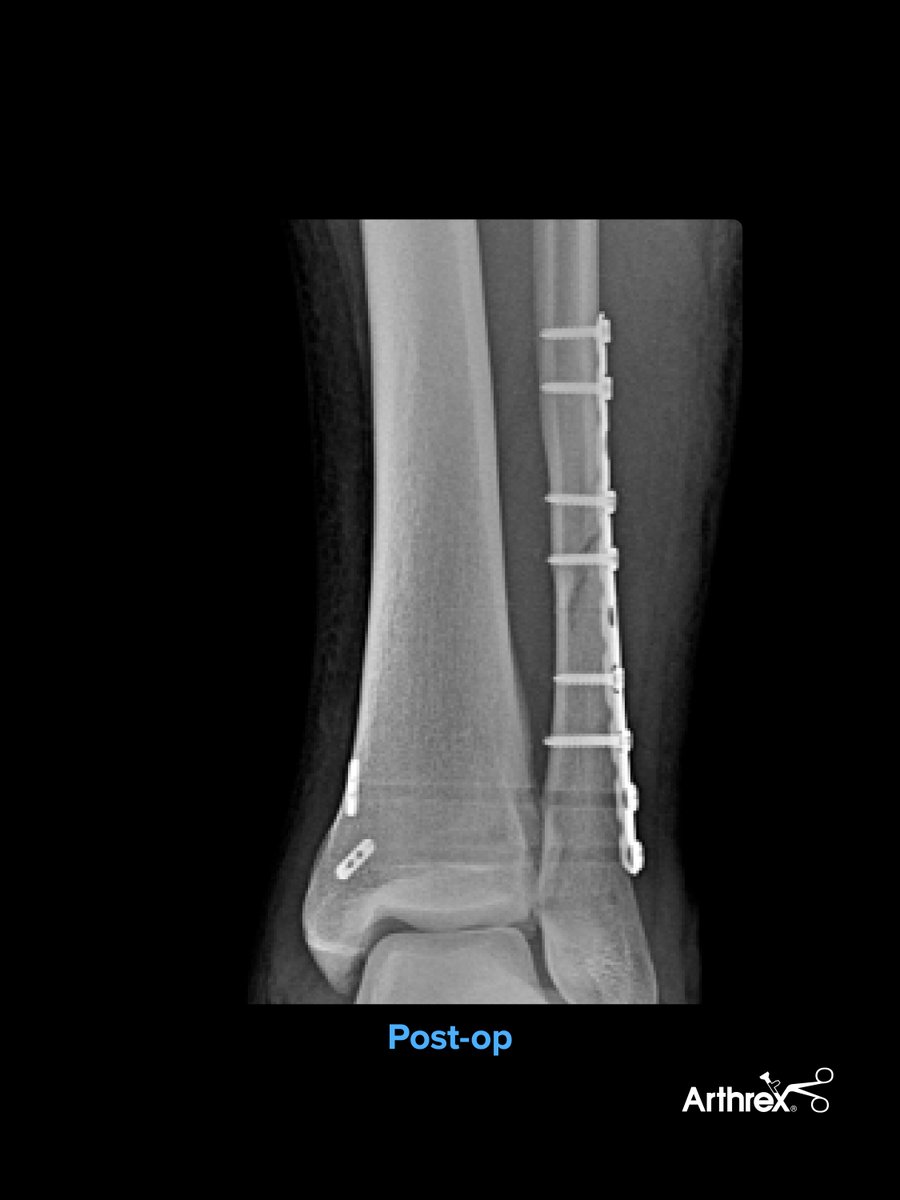

Case Review: Ankle Fracture, InternalBrace™ Ligament Augmentation Repair, and Syndesmosis TightRope® XP Implant System A 22-year-old male sustained an isolated rotation ankle injury while playing football. The mechanism of injury was a direct lateral force by another player, followed by external rotation. X-rays showed a proximal Weber C oblique fibular fracture with widening of the tibiotalar clear space and medial clear space. Surgical Technique Establish standard anterior medial and anterolateral portals. Introduce the NanoScope™ through the anteromedial portal. Debride the acute synovitis and hemorrhagic plug as well as the syndesmosis. Direct lateral approach — Apply a fibular ORIF using a long 1⁄3 tubular plate in a posterolateral fashion. Clamp the plate to the bone and use as a reduction tool, which is useful with more proximal short oblique fibular fractures. Inspect and debride the syndesmosis and reduce manually with temporary K-wire fixation. Debridement is critical to ensure no soft tissue or bone will impede the fibula from falling back into the tibial incisura. Multiligament stabilization of the syndesmosis 1. Secure the InternalBrace ligament augmentation repair into the distal fibula in an anterior-to-posterior fashion using a 3.5 mm SwiveLock® anchor. 2. Prep the anterolateral tibia for the 4.75 mm SwiveLock anchor using a 3.4 mm drill and 4.75 mm tap. Leave the tap in the tibia until the TightRope implants are placed to avoid drilling into the anchor. 3. Insert 2 Syndesmosis TightRope XP implants through the end of the ⅓ tubular plate. 4. Insert the SutureTape into the anterolateral tibia using a 4.75 mm SwiveLock anchor to close down the anterior syndesmosis. Courtesy of Spencer Monaco, DPM Learn more: arthrex.info/4bAa10C